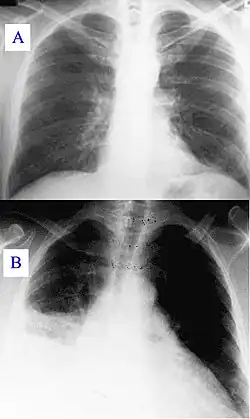

O período de incubação é de duas a três semanas. E geralmente é assintomática, sendo que seus possíveis sintomas incluem[5] :

- Tosse seca;

A Febre Q é uma causa reconhecida de abortos, natimortos e baixo peso ao nascer em ruminantes e animais de companhia. Casos de infeção por C. burnetii no gado são monitorados, vacinados e estudados por associação com pneumonia, doenças respiratórias, cardíacas e reprodutivas no Canadá, EUA, Chipre, França, Hungria, Japão, Suíça e Alemanha. [6]